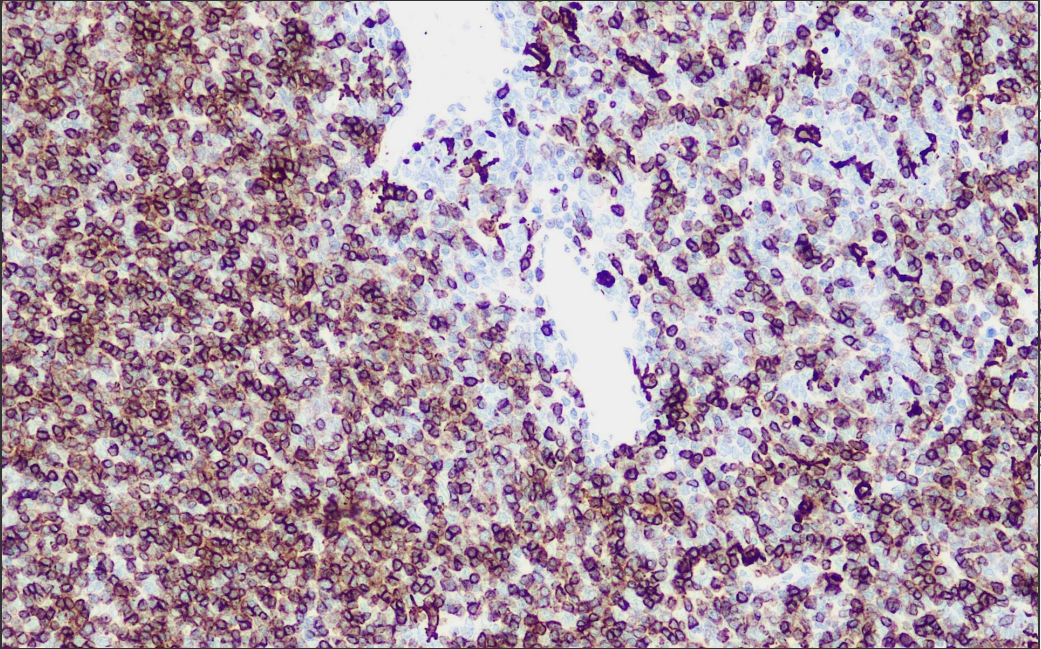

Positive Control: Thymus

CD1a is a membrane surface protein with a molecular weight of 43-49 kD, which is mainly expressed in thymic cortical cells, cutaneous Langerhans cells, and dendritic cells of the dermis, etc. In certain malignant tumors, the expression of CD1a has a certain correlation with the prognosis, recurrence and metastasis of tumors.

CD1a Antibody Reagent binds specifically to CD1a molecular antigen. Immunohistochemistry kits containing CD1a Antibody Reagent are suitable for the precise diagnosis of leukemia, Lonhans histiocytosis and lymphoma.